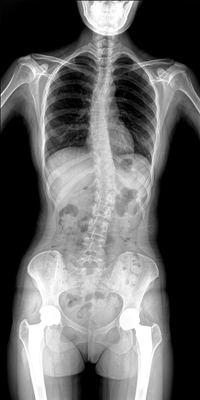

臨床需要對患者的脊柱情況有全面了解,故而術(shù)前術(shù)后均需要均需要借助DR拍攝X光片便于分析病情、明確診斷及術(shù)后觀察治療效果。大視野動(dòng)態(tài)DR可以對患者的脊柱進(jìn)行長尺寸攝影,一次拍攝就能獲取完整的脊柱全景圖像。診斷醫(yī)生通過拍攝后的影像測量全脊柱的生物角度、Cobb角等,為脊柱側(cè)彎的畸形矯正患者術(shù)前術(shù)后的檢查提供重要的診斷依據(jù)。

通過大視野動(dòng)態(tài)DR進(jìn)行全脊柱攝片,其得到的影像密度均勻、清晰、接緣處過渡自然。且操作更加便捷,不需要二次攝片然后進(jìn)行圖像拼接,拍攝時(shí)間短,效率高。在減少輻射劑量的同時(shí)也能為臨床醫(yī)生帶來更精確的診斷信息。非拼接影像可保證雙腿測量(如力線)數(shù)據(jù)的準(zhǔn)確性,有效避免攝影信息的丟失。給手術(shù)醫(yī)生提供準(zhǔn)確的術(shù)前診斷數(shù)據(jù),提高手術(shù)成功率。

綜上所述,大視野動(dòng)態(tài)DR進(jìn)行全脊柱成像能夠清晰的呈現(xiàn)骨關(guān)節(jié)結(jié)構(gòu),可以在全景脊柱圖像基礎(chǔ)上對角度值進(jìn)行測量,能夠很好的反映骨骼的真實(shí)比例與長度,為臨床診斷和治療提供了更精確的數(shù)據(jù),有著重要臨床應(yīng)用價(jià)值。